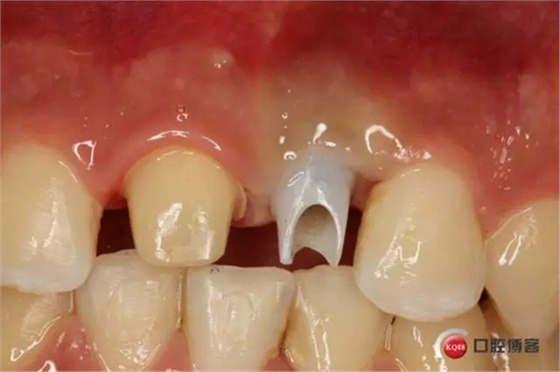

種植后修復,我們要把握每一個細節(jié),比色,轉(zhuǎn)移桿的就位,我們必須把臨床做好,技工師傅才會給我們做出好的修復體,減少一些不必要的失誤,首先術前的檢查是必要一步 ,再是器械的準備使我們臨床操作有條不紊,術前拍照,o-bite取咬合記錄,消毒修復術區(qū),旋出愈合基臺,生理鹽水沖洗袖口,拍照袖口,安放合適轉(zhuǎn)移桿,拍X線見轉(zhuǎn)移桿就為良好,硅橡膠取模,術后旋回愈合基臺,拍照比色。

藻酸鹽對頜取模,超硬石膏灌注。發(fā)加工廠,與技工溝通注意事項,等修復體做好后,檢查模型。是否就位,是否密合,預約患者復診戴牙,消毒修復區(qū),旋出愈合基臺,定位器指導安放修復基臺,試戴冠,調(diào)磨鄰接及 咬合至合適,拋光,患者滿意,加力扳手加力至30N,拍X片見就位良好,特芙蓉及暫封膏封中央螺絲孔,聚羧酸鋅粘固劑粘固,或是樹脂水門汀粘固,清理多余粘結(jié)劑,光固化樹脂封螺絲孔,拋光。術后注意隨訪。